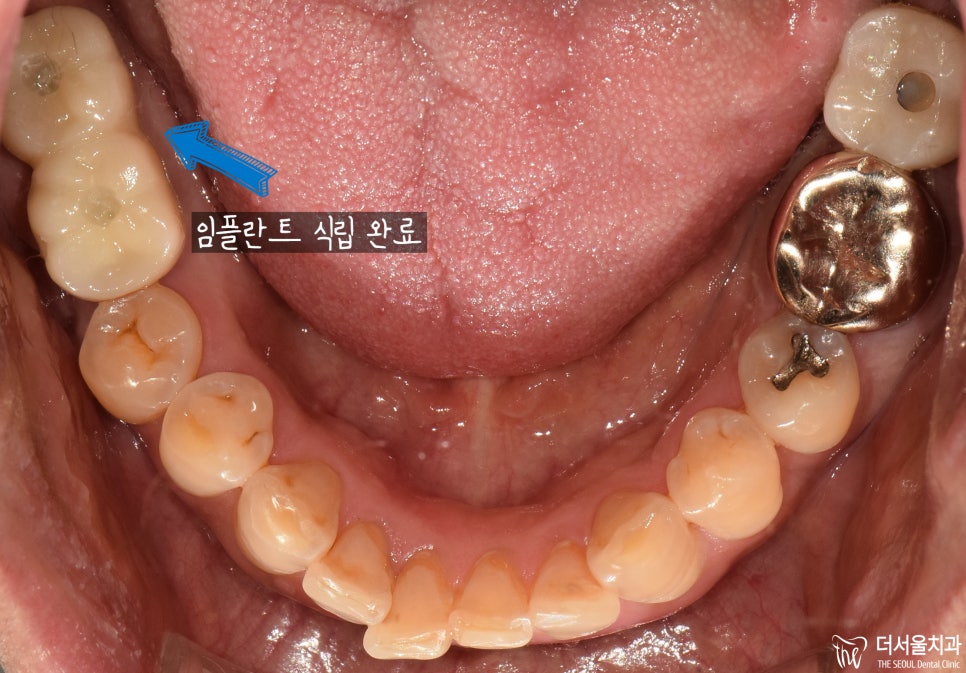

『결과

판교역 치과 추천』

깔끔하게 임플란트 수술을 잘 끝냈으며,

환자분 또한 잘 심어주셨다며

결과에 흡족해하셨습니다.